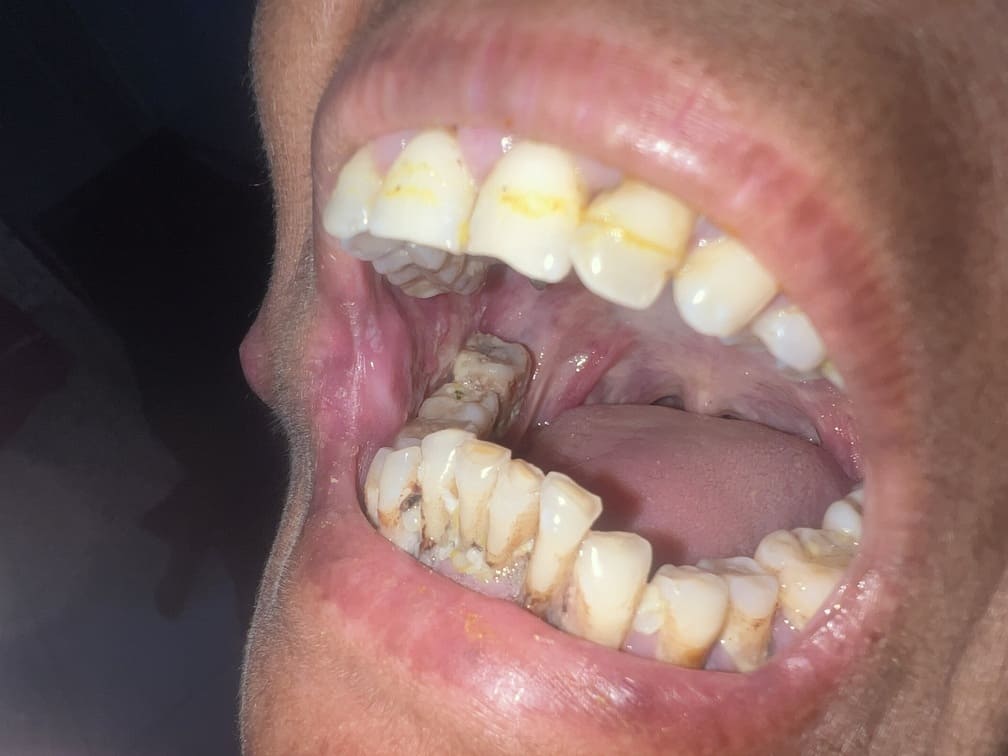

57 years old female suffering from left buccal mucosa growth involving left RNT and gingival surface of lip extending up to right angle mouth.left modified neck dissection with left distal segmental mandibulectomy with wide excision of left buccal mucosa with left RMT growth with excision gingival margin of lower lip with left pectoralis with right nasolabial flape done.

29-12-2025